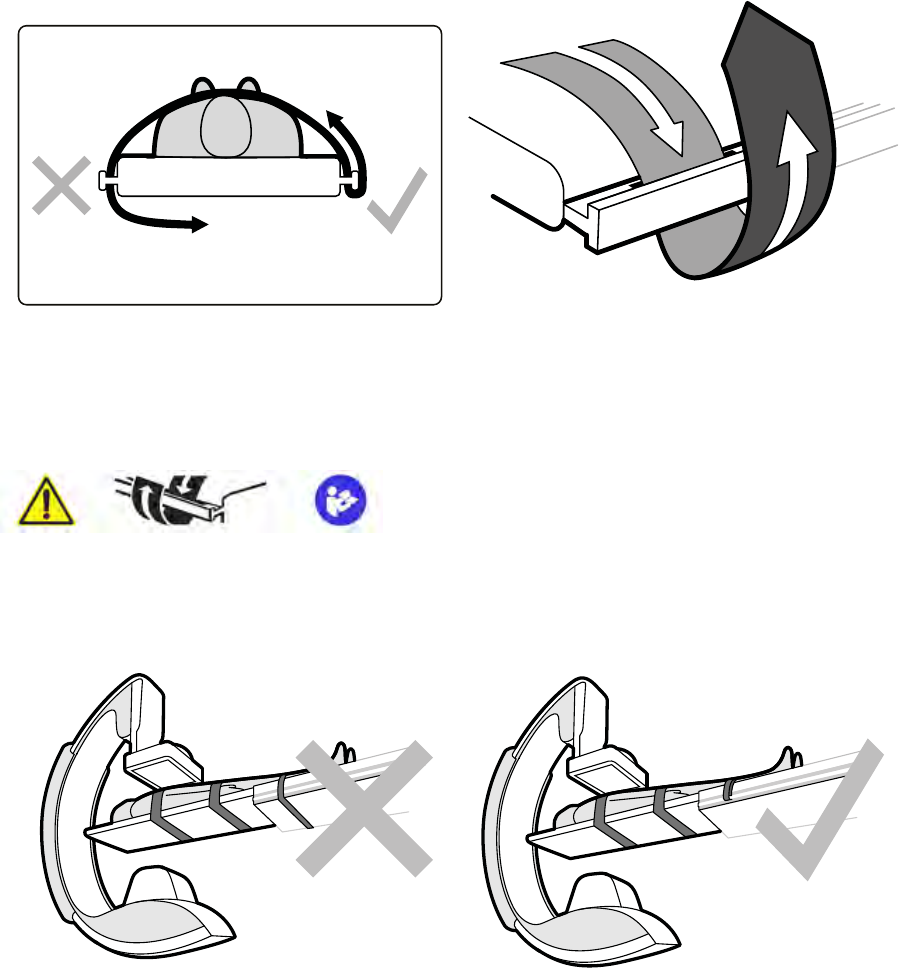

14.2 Zdejmowanie i zakładanie kratki przeciwrozproszeniowej...................................................252

14.2.1 Zdejmowanie kratki przeciwrozproszeniowej...................................................... 252

14.2.2 Mocowanie kratki przeciwrozproszeniowej......................................................... 253